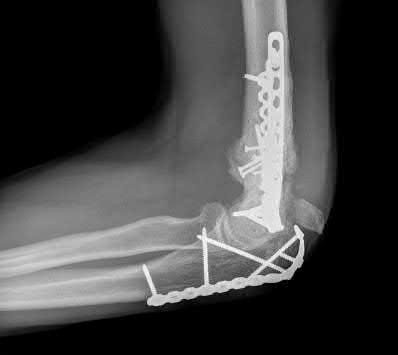

A 51-year-old carpenter presents with a distal humerus nonunion (Figures A and B). After repair of the nonunion, he is lost to follow up for 3 months and then presents to your clinic pain-free and with evidence of fracture union. On examination the elbow arc of motion is 10-80 degrees. Following a brief failed trial of conservative management, you recommend:

Limited flexion outside a functional range of motion (30-130 degrees) can be quite debilitating, and it is often addressed with open release of the posterior bundle of the MCL and posterior capsule and excision of osteophytes.

A frequent complication of distal humerus fractures is post-traumatic stiffness. This patient has had multiple procedures about the distal humerus, and the question stem implies that he did not complete a structured range of motion protocol following the repair of his nonunion. Beyond a trial of conservative management, there are many techniques described for capsule and soft tissue releases as well as bony resections if heterotopic ossification is present. This patient's severely limited flexion would best be addressed with a release of the posterior bundle of the MCL, and with flexion